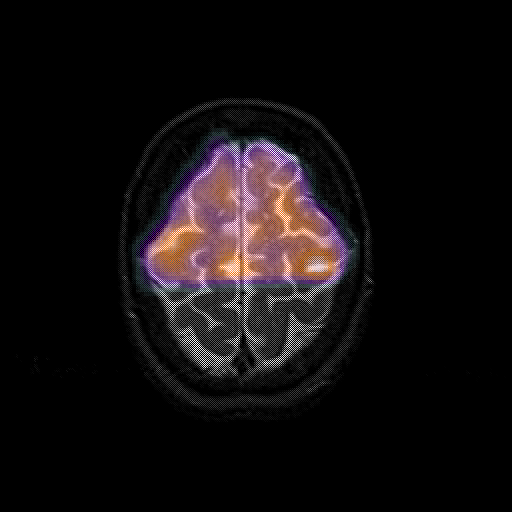

overlay 1: Slice 44

Slice 44

MRCBFCBF with

T1PDT2T1PDT2